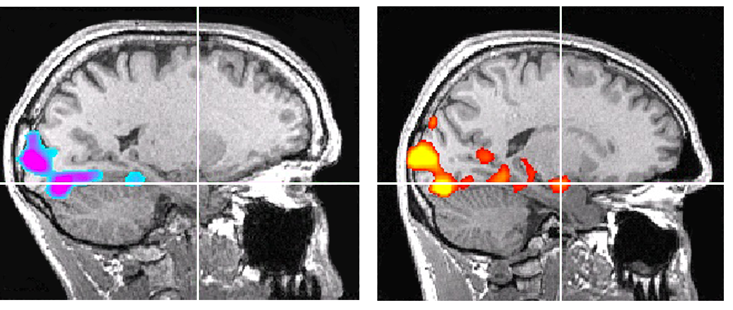

Even to the untrained eye, the reason for her interest is clear. Joseph had used a control subject—a high-sensation-seeking male rock climber of similar age to Honnold—for comparison. Like Honnold, the control subject had described the scanner tasks as utterly unstimulating. Yet in the fMRI images of the two men’s responses to the high-arousal photographs, with brain activity indicated in electric purple, the control subject’s amygdala might as well be a neon sign. Honnold’s is gray. He shows zero activation.

Flip to the scans for the monetary reward task: Once again, the control subject’s amygdala and several other brain structures “look like a Christmas tree lit up,” Joseph says. In Honnold’s brain, the only activity is in the regions that process visual input, confirming only that he had been awake and looking at the screen. The rest of his brain is in lifeless black and white.

Nowhere in the fear center of Honnold’s brain could the neuroscientist spot activity.